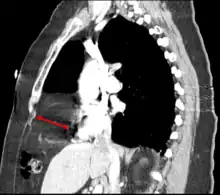

CT of the chest demonstrates a Morgagni hernia (red arrow)

This rare anterior defect of the diaphragm is variably referred to as a Morgagni, retrosternal, or parasternal hernia. Accounting for approximately 2% of all CDH cases, it is characterized by herniation through the foramina of Morgagni which are located immediately adjacent and posterior to the xiphoid process of the sternum.[4]